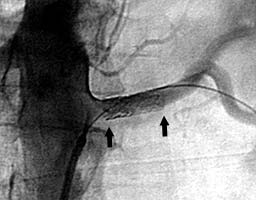

В суженную артерию установлен стент (границы стента отмечены черными стрелками). Проходимость артерии восстановлена. |